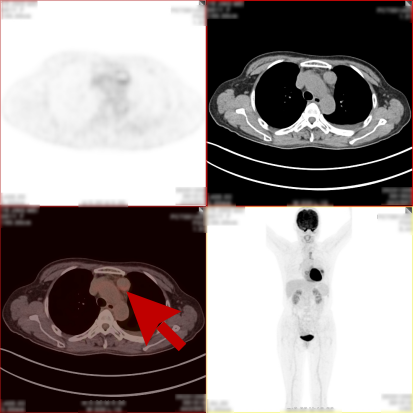

病史:女,51岁,左侧胸腔肿物约3-4年,干咳伴左侧胸痛1个月余,自服药物不能缓解。2023.12.6 CT 显示左侧胸腔及纵隔内肿块,考虑肿瘤性病变,胸膜来源低度恶性肿瘤(胸膜间皮瘤)可能。无其他病史,进食可,二便可,今年以来有体重减轻,为鉴别病灶良恶性申请PET/CT检查。

PET/CT检查所见

PET/CT诊断意见:

1、左侧胸腔内混杂密度肿块,实性组织代谢轻中度增高,考虑间叶组织来源低度恶性肿瘤,病灶内部分组织坏死,与左侧胸膜粘连并向纵隔内生长;

2、纵隔(1L、2L、3A、6、8R 组)及左侧锁骨上窝多发淋巴结转移灶;

3、胸 8 椎体左份结节状高代谢病灶,考虑骨转移灶。

PET/CT活检病理:恶性畸胎瘤